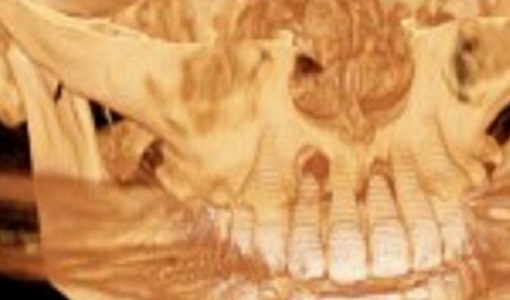

口腔外科(インプラント)、歯科・矯正歯科(歯列矯正)、 アメリカ式の根管治療(Endodontics,Rootcanal treatment),を中心に

虫歯治療、歯周病治療(歯槽膿漏)を総合的に治療し、お口の健康と若さを維持する治療を行っております。